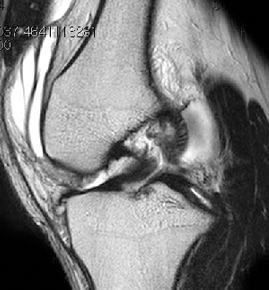

• ACL 손상 방사선 사진2